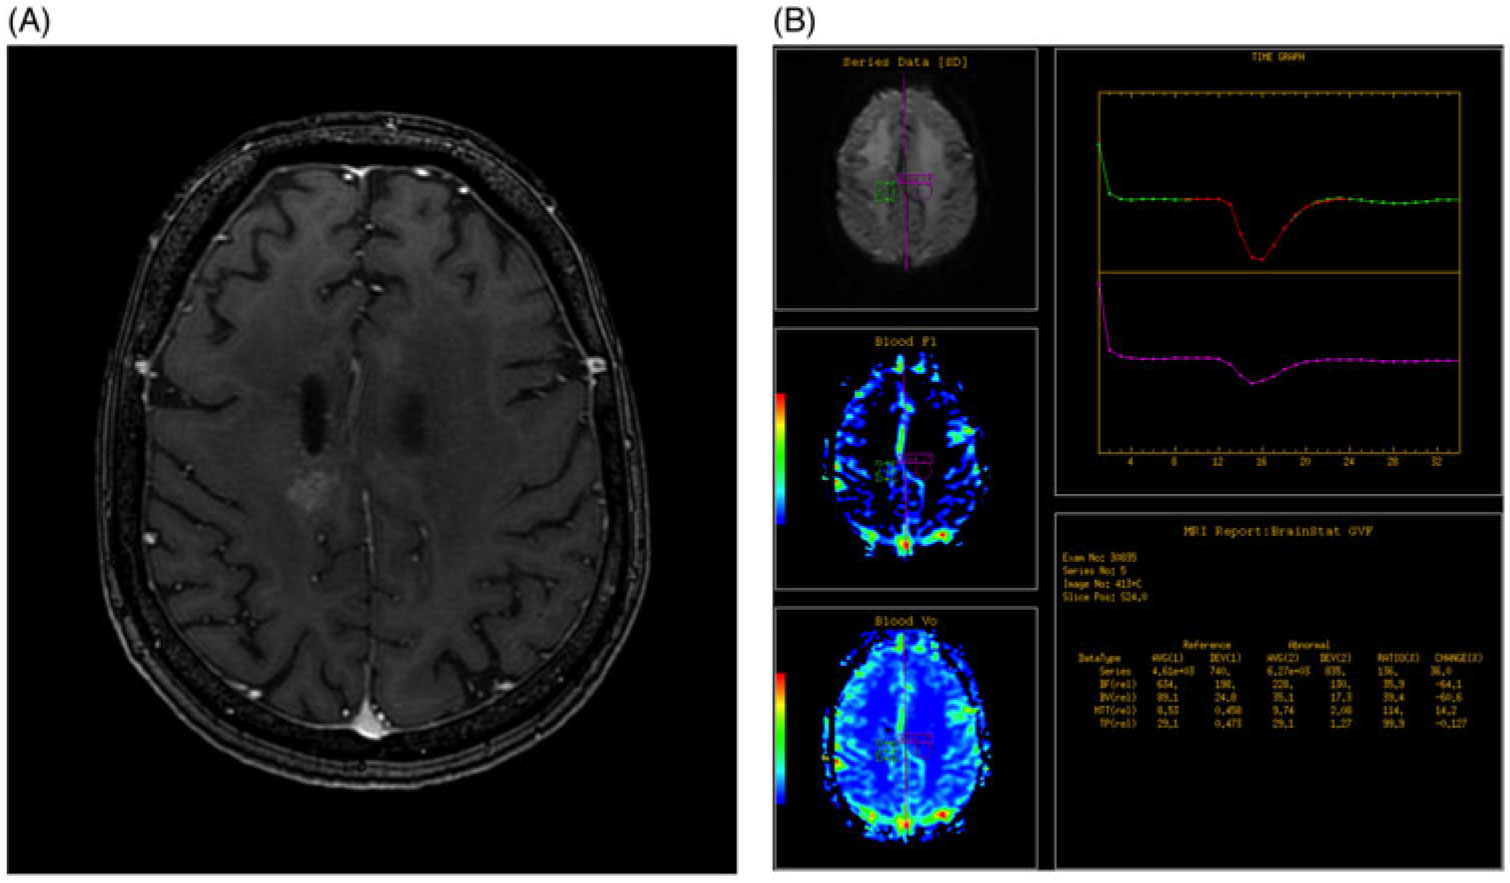

A region of interest (ROI) was selected by the radiologist on the conventional MRI post-gadolinium enhanced T1 images (Figure 1A and B). The ROI was then compared to the normal contralateral brain parenchyma at the same level to determine the relative cerebral blood volume (rCBV). Increased rCBV equated to a positive DSC-MRP while equal or decreased rCBV equated to a negative DSC-MRP.

Figure 1. (A) Axial post-gadolinium enhanced T1 fat saturated image of the brain demonstrates abnormal heterogeneous enhancement within the high right frontoparietal lobe, adjacent to the site of previous resection. (B) DSC-MRP was determined by assessing a region of interest based on the site of abnormal enhancement, as determined by an experienced radiologist (green circle) and compared to the contralateral normal brain parenchyma (purple circle). Graph depicts the change in perfusion over time for the two ROIs and the calculated values are used to generate color maps.